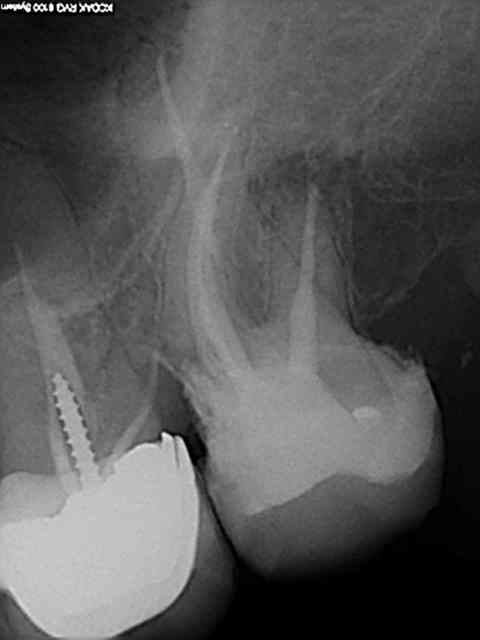

Exemple concret, de ce samedi (exceptionnellement au boulot car c'est un pote qui travaille sur Paris et qui a une semaine de vacances), j'en ai tous les jours.

la première radio date de 2011 issue d'un status inutile selon la sécu. Suspicion de reprise en mésial sous l'onlay de 27, noté sur le dossier à surveiller. Le patient appelle pour douleurs lancinantes spontanées la semaine dernière en haut au fond et à gauche exacerbées par le froid.

Diagnostic clair net et précis et par téléphone en plus : ca n'est pas du au tt merdique de la 26. Ce qui est confirmé in situ par la radio numéro 2 prise le jour meme de l'endo.

Comme à mon habitude je m'excuse d'avoir irradié le patient copieusement ( à raison de 70 kv et 0,099 s par cliché) plutot qu'un seul cliché argentique en fin de tt ( 70 kv aussi mais 1,3 s d'exposition lui) développé en fin de journée comme ca a du etre le cas pour le tt de 26 ( et m... encore raté).

Je sais pas moi mais le résultat parle de lui meme ( putain de mv2 que j'ai réussi à choper dans un 2 eme temps une fois les autres obturés)

Taille empreinte provisoire dans la foulée , l'avantage de la gutta chaude.

Vous préférez quoi dans votre bouche ? une seule radio et un tt endo comme la 26 ou 6 clichés et mon tt endo de 27 ?